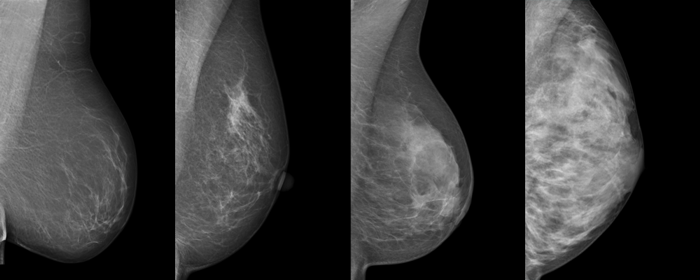

Die vier Dichtegrade der Brust in der Mammographie

Das folgende Bild zeigt typische Beispiele für die vier Brustdichtegrade in der Mammographie:

Die dichten, (in der Mammographie hellen) Bezirke entsprechen dabei Brustdrüsengewebe, während die dunklen, 'transparenten' Bezirke Fettgewebe entsprechen, da Fettgewebe für Röntgenstrahlen wesentlich 'durchsichtiger' ist als Drüsengewebe.